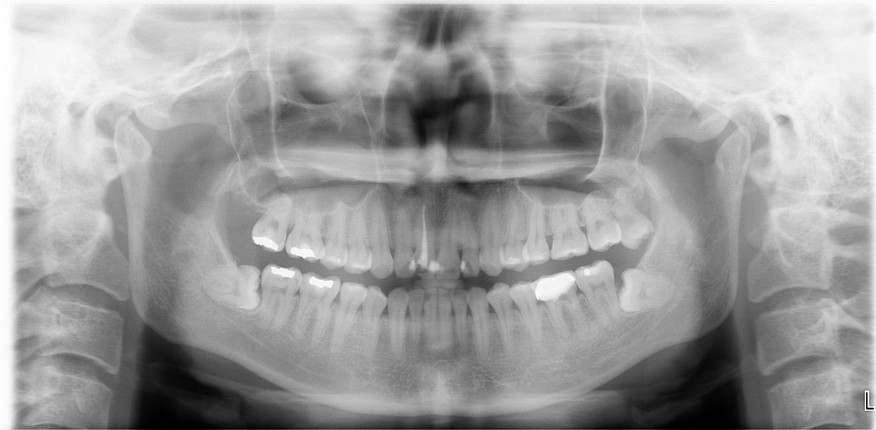

治療前,環口X光,阻生齒